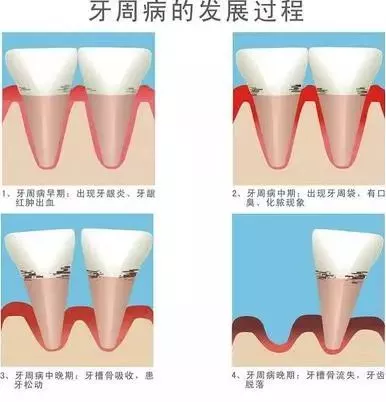

牙周炎,目前临床牙医也什么太好的方法,一般即是帮患者洗牙,做龈下刮治,再配合一些消炎药暂时缓解一下。牙周炎的病理影响,如果不重视护理会导致牙龈出现局部营养功能障碍,牙龈无法通过消化吸收到足够维生素养分,长期处于营养不良状态而导致牙龈萎缩。

牙龈出血是诊断牙龈炎的金指标,也是活动性牙周炎的一项预测指标。如果经常出现牙龈出血,或存在红肿、退缩、肥大增生、口臭等问题,就要加以警惕,及时到口腔科就诊。等到牙齿松动移位、咀嚼无力时往往就发展到较严重的程度了。